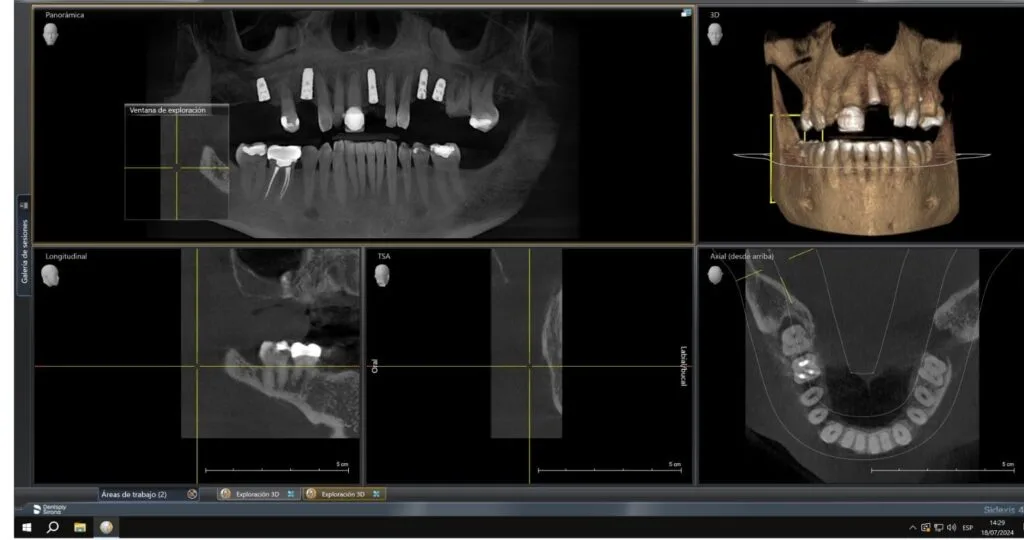

Este paciente presenta la pérdida de cinco piezas dentales y cuenta con un hueso maxilar en óptimas condiciones para la colocación de implantes dentales.

Nuestra consulta es muy detallada; te explicamos cada paso del tratamiento utilizando tus propias imágenes para una mejor comprensión.

Nuestra tecnología de vanguardia, como la tomografía 3D y la planificación virtual de implantes, asegura que el implante se coloque en la posición más adecuada para tu anatomía bucal.

La tomografía 3D es una herramienta clave en las consultas iniciales, ya que nos permite obtener una imagen precisa de tu estructura ósea y planificar el tratamiento con exactitud. Esto no solo mejora la precisión del procedimiento, sino que también reduce los riesgos y aumenta las probabilidades de éxito.